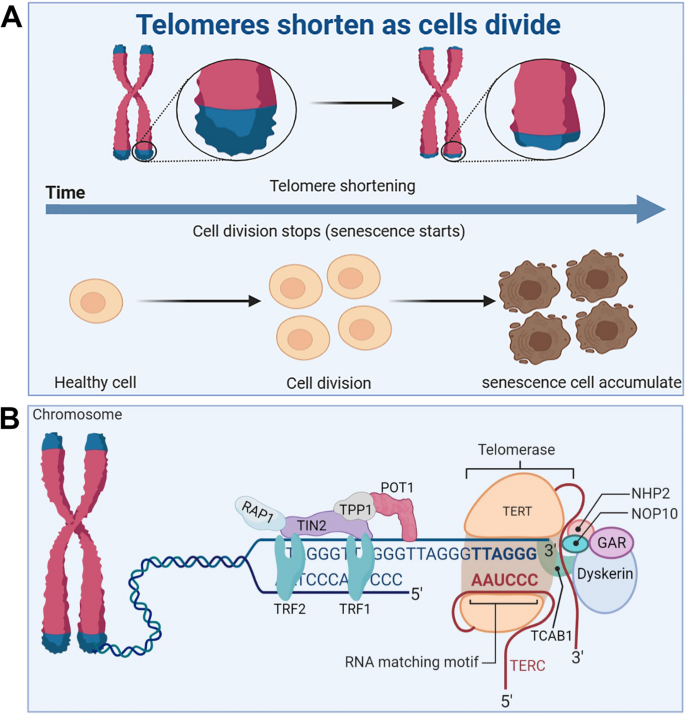

Telomeres are small stretches of DNA-protein complexes present at the ends of linear chromosomes in eukaryotic cells, which maintain chromosomal integrity, control the cell division cycle, and are essential for an organism’s healthy life span and reproduction [ 61 ]. As early as the 1960s, a scientist named Leonardo Hayflick discovered that cultured human fibroblasts had limited and reproducible replication capacity and were governed by cell-autonomous mechanisms [ 62 , 63 ]. Even if the cold stops the cell division, once the temperature rises again, the cells will continue to divide before freezing, until 50 times after the cessation of division. Heverick realized that cells have a deep-seated internal mechanism that controls the number of times they divide [ 64 ]. In the 1970s, Olovnikov [ 65 ] and Watson [ 66 ] discovered the “end duplication problem” by looking at asymmetries in linear DNA replication and predicting that each cell division results in chromosomal DNA at the ends of the lagging strands loss, eventually leading to the gradual shortening of chromosomes. Limited telomere length reserve is an obstacle to cell proliferation and viability, and the loss of telomere function is closely associated with age-related functional decline and increased incidence of disease [ 67 ] (Fig. 3 A).

Telomere and telomerase structure, and their relationship with cell senescence. A Telomeres shorten during cell division, leading to accumulation of senescent cells. B The structure of the telomere-telomerase complex. TERT, telomerase reverse transcriptase; TERC, telomerase RNA component; NOP10, nucleolar protein family A, member 3; NHP2, nucleolar protein family A, member 2; GAR, nucleolar protein family A; TIN2, TERF1-interacting nuclear factor 2; TPP1, telomere protection protein 1; TRF1, telomeric repeat binding factor 1; TRF2, telomeric repeat binding factor 2; POT1, protection of telomeres 1; RAP1, TERF2-interacting protein. The telomere diagram is derived from “biorender”

Telomere and telomerase structure

Telomere end protection is evolutionarily highly conserved from lower to higher multicellular organisms [ 68 ]. Structurally, telomeres consist of repeating nucleotide sequences 3’-[TTAGGG]-5’ in tandem, ranging from a few to tens of bases, terminated at the 3’ end by a single strand of guanine-rich nucleotides of 75 to 300 nt, forming a “cap structure” (Fig. 3 B). Telomeres are covered by a special protein called the shelterin complex, which is a multimer of six protein subunits (TRF1, TRF2, TPP1, POT1, TIN2, and RAP1) that work together to protect the chromosomes and regulate telomere length [ 68 ]. Telomeres and shelterin complexes form a sophisticated higher-order structure that protects DNA repair programmes from fusing ends by mediating non-homologous end-joining of telomeric DNA through double-stranded DNA break detection, ultimately involved in the capping, protection, and regulation of telomeres [ 69 ]. Correspondingly, mutations in these six protein components can disrupt the shelterin-telomere complex, resulting in terminal fusion and premature senescence. Specifically, telomere maintenance is inseparable from normal expression of TRF1 [ 70 , 71 ]. TRF1 deletion induces telomeric DNA to form a fragile site phenotype, whereas TRF1 overexpression impairs telomerase binding to telomere ends, eventually resulting in telomere shortening [ 72 , 73 ]. TRF2 folds telomeric DNA into T-loops, inhibits the ataxia telangiectasia mutated-dependent DDR at chromosome ends, and suppresses end-to-end chromosome fusion and canonical homologous end joining [ 74 ]. In addition, TIN2 plays a connecting role in the shelterin complex and forms bridges between different shelterin proteins [ 75 ]. TIN2 mutations do not interfere with the spatial structure of other shelterin components on telomeres; however, the TIN2-R282H mutation activates telomeric DNA damage signalling, which results in telomere instability associated with telomerase activity, eventually leading to a premature cellular senescence phenotype [ 76 ]. Uncontrolled POT1 impairs telomerase binding to telomere ends, resulting in shortened telomeres [ 77 ]. TPP1 interacts with telomerase reverse transcriptase (TERT) to recruit telomerase and its loss elicits a robust telomeric DNA damage response [ 78 ]. Rap1 is a key telomere-capping protein that prevents non-homologous end joining and telomere fusion, and its overexpression causes histone loss and accelerates cellular senescence [ 79 , 80 ]. Overall, the biological functional integrity of telomeres depends on the interaction of telomeres and the shelterin complex, which together regulate telomere length and the cell life cycle. It should be noted that normally shortened telomeres alone do not drive senescence (biology) if telomeres become so short that they are perceived as double-stranded DNA breaks, then these telomeres will recruit the DDR and induce the cells into a normal apoptotic or senescence program.

Telomerase is a riboprotease composed of two basic subunits: TERT and telomerase RNA component (TERC) [ 81 ]. The H/ACA domain of Cajal body protein 1 in TERC binds to telomerase to form telomerase Cajal body protein 1, which catalyzes telomerase activity and transports telomerase to the ends of telomeres [ 82 ]. In addition, multiple core protein components, including dyskerin, NHP2, NOP10, and GAR1, are essential for the normal catalytic function of telomerase [ 83 ]. Normally, telomerase is abundantly expressed in undifferentiated stem [ 67 ] and progenitor cells of germ cells [ 84 ], the skin, intestine [ 85 ], haematopoietic system [ 82 ], hair bulge [ 86 ], and testis [ 7 ]. Nevertheless, it is extremely low or undetectable in differentiated adult cells, such as neuroblasts [ 87 ], fibroblasts [ 88 ], cardiomyocytes [ 89 ], and sperm cells [ 90 ]. In the germ line and in some stem cells, telomerase can compensate for this loss of telomere duplication, which decreases with cell division [ 91 ]. Telomerase is silent during the early development of most somatic cells, limiting the number of cell divisions until the telomeres become very short [ 92 ]. The pathogenicity of telomere shortening during aging is a characteristic antagonistic pleiotropic effect. On the one hand, cells with telomere dysfunction are prone to genome instability and may become cancer cells. On the other hand, the normal replicative shortening of telomeres can restrict unrestricted cell proliferation and induce cell apoptosis or senescence, thus preventing the formation of tumors. Robinson et al. found a way to help telomeres maintain their length, a technique known as alternative lengthening of telomeres (ALT) [ 93 ]. In osteosarcoma and bread cancer cell lines, the potential relationship between telomere lengthening and inhibition of tumor growth is cleverly orchestrated in cell lines that maintain telomere length by the ALT [ 94 ]. It helps that tumors can be suppressed even when telomeres are lengthened.

Maintenance of adequate telomere length in normal cells requires intact telomere structure and highly sophisticated regulation of telomerase [ 95 ]. However, each associated protein in the telomere and telomerase complexes is susceptible to uncontrollable factors in the tissue microenvironment [ 96 ]. However, there is still some scientific debate regarding how the telomerase complex is sensed, expressed, and recruited to telomere ends for functional regulation to determine the role of telomeres and telomerases in the pathogenesis of systemic aging and degenerative diseases. Recently, telomere dysfunction has been described as a molecular feature of senescent cells, and the loss of telomere function is closely associated with genomic instability [ 97 ], DDR [ 98 ], and age-related decline in fitness [ 99 ]. Most importantly, telomere dysfunction during aging can amplify and drive other aging mechanisms and the progeria syndrome.

Relationship between telomere and telomerase dysfunction and aging

Organismal cellular telomere reserves are limited, and the loss of telomere function is closely associated with age-related adaptive decline [ 99 , 100 , 101 ] (Fig. 4 ). Excellent telomere and telomerase structures are essential for ensuring the normal physiological function of mothers and offspring, and their integrity has a certain genetic intergenerational effect [ 102 , 103 ]. Mice with knockout of TERT that are crossbred in successive generations, the telomeres of the offspring gradually shorten, finally developing telomere dysfunction in the third generation [ 104 ]. Additionally, low telomerase levels and continued tissue turnover lead to decades of progressive telomere attrition in the progenitor cells of highly proliferative tissues, including the haematopoietic system, gastrointestinal tract, and skin [ 10 , 11 ]. Excessive telomere attrition ultimately triggers DDR such as cell cycle arrest [ 105 ], apoptosis [ 106 , 107 ], differentiation disorders [ 108 ] and senescence [ 109 ]. Notably, as the aging process progresses, hypoproliferative tissues, including the heart, brain, and liver, may suffer from the effects of reactive oxygen species (ROS), which further induce telomere sequence damage, telomere attrition, and uncapping [ 86 , 110 ]. Thus, the aforementioned telomere properties make them a focal point in the biology of aging.

Telomere dysfunction activates DDR to drive cellular senescence. ROS induce telomere sequence damage, leading to telomere shortening and decapitation, triggering DDR, inducing the overexpression of cell cycle inhibition markers p53 and p21, and accelerating cell senescence. Senescent cells secrete SASP, which alter extracellular matrix composition, recruit and enhance T cells and macrophages, which can spread the aging phenotype to surrounding cells, thus promoting systemic chronic inflammation and inflammation-related diseases

Shortening of telomeres to a critical length leads to replicative cellular senescence [ 86 , 111 , 112 , 113 ]. Chromosomal telomeres gradually shorten as DNA replicates. When telomeres reach a critical length, they cannot bind enough telomere-covering proteins and are perceived as exposed DNA ends [ 114 ]. One or a few very short telomeres are sufficient to trigger the DNA damage response and induce overexpression of the cell cycle inhibitory markers p53 and p21, thereby forcibly inhibiting cell proliferation [ 115 ]. Accumulated senescent cells secrete a complex set of pro-inflammatory cytokines, termed the senescence-associated secretory phenotype (SASP), including interleukins, interleukin chemokines, proteases, and growth factors. The SASP alters the composition of the extracellular matrix and propagates the senescent phenotype to surrounding cells, leading to systemic chronic inflammation [ 116 ]. Interestingly, persistent telomere cohesion protected aged cells from premature senescence [ 117 ]. Therefore, telomere dysfunction-associated DNA damage response signalling events are key determinants of cell fate and organismal aging.

In summary, telomeres and telomerase play important roles in the core mechanisms that drive aging and many major human diseases. However, many knowledge gaps remain, such as the elucidation of the mechanisms regulating telomerase expression and activity, the non-canonical function of TERT, and the interactions between telomere dysfunction, inflammation, fibrosis, and degenerative disease. Therefore, there is an urgent need to develop telomerase activators for the treatment of aging and age-related diseases to prevent and treat fatal diseases caused by telomere shortening by rescuing telomeres and telomerase damage.